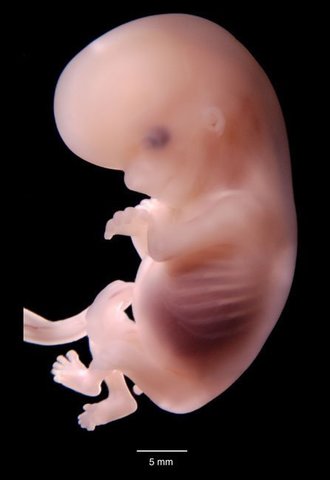

En la quinta semana de embarazo, elembrión mide 6 mm.

Su cabeza se separa del cuerpo y su cola desaparece. A ambos lados de la cabeza se distinguen dos manchas negras: los ojos. Unas pequeñas yemas que formarán los brazos y las piernas empiezan a tomar forma alargada.

El hígado y los riñones están ya prácticamente formados en este estadio del embarazo.